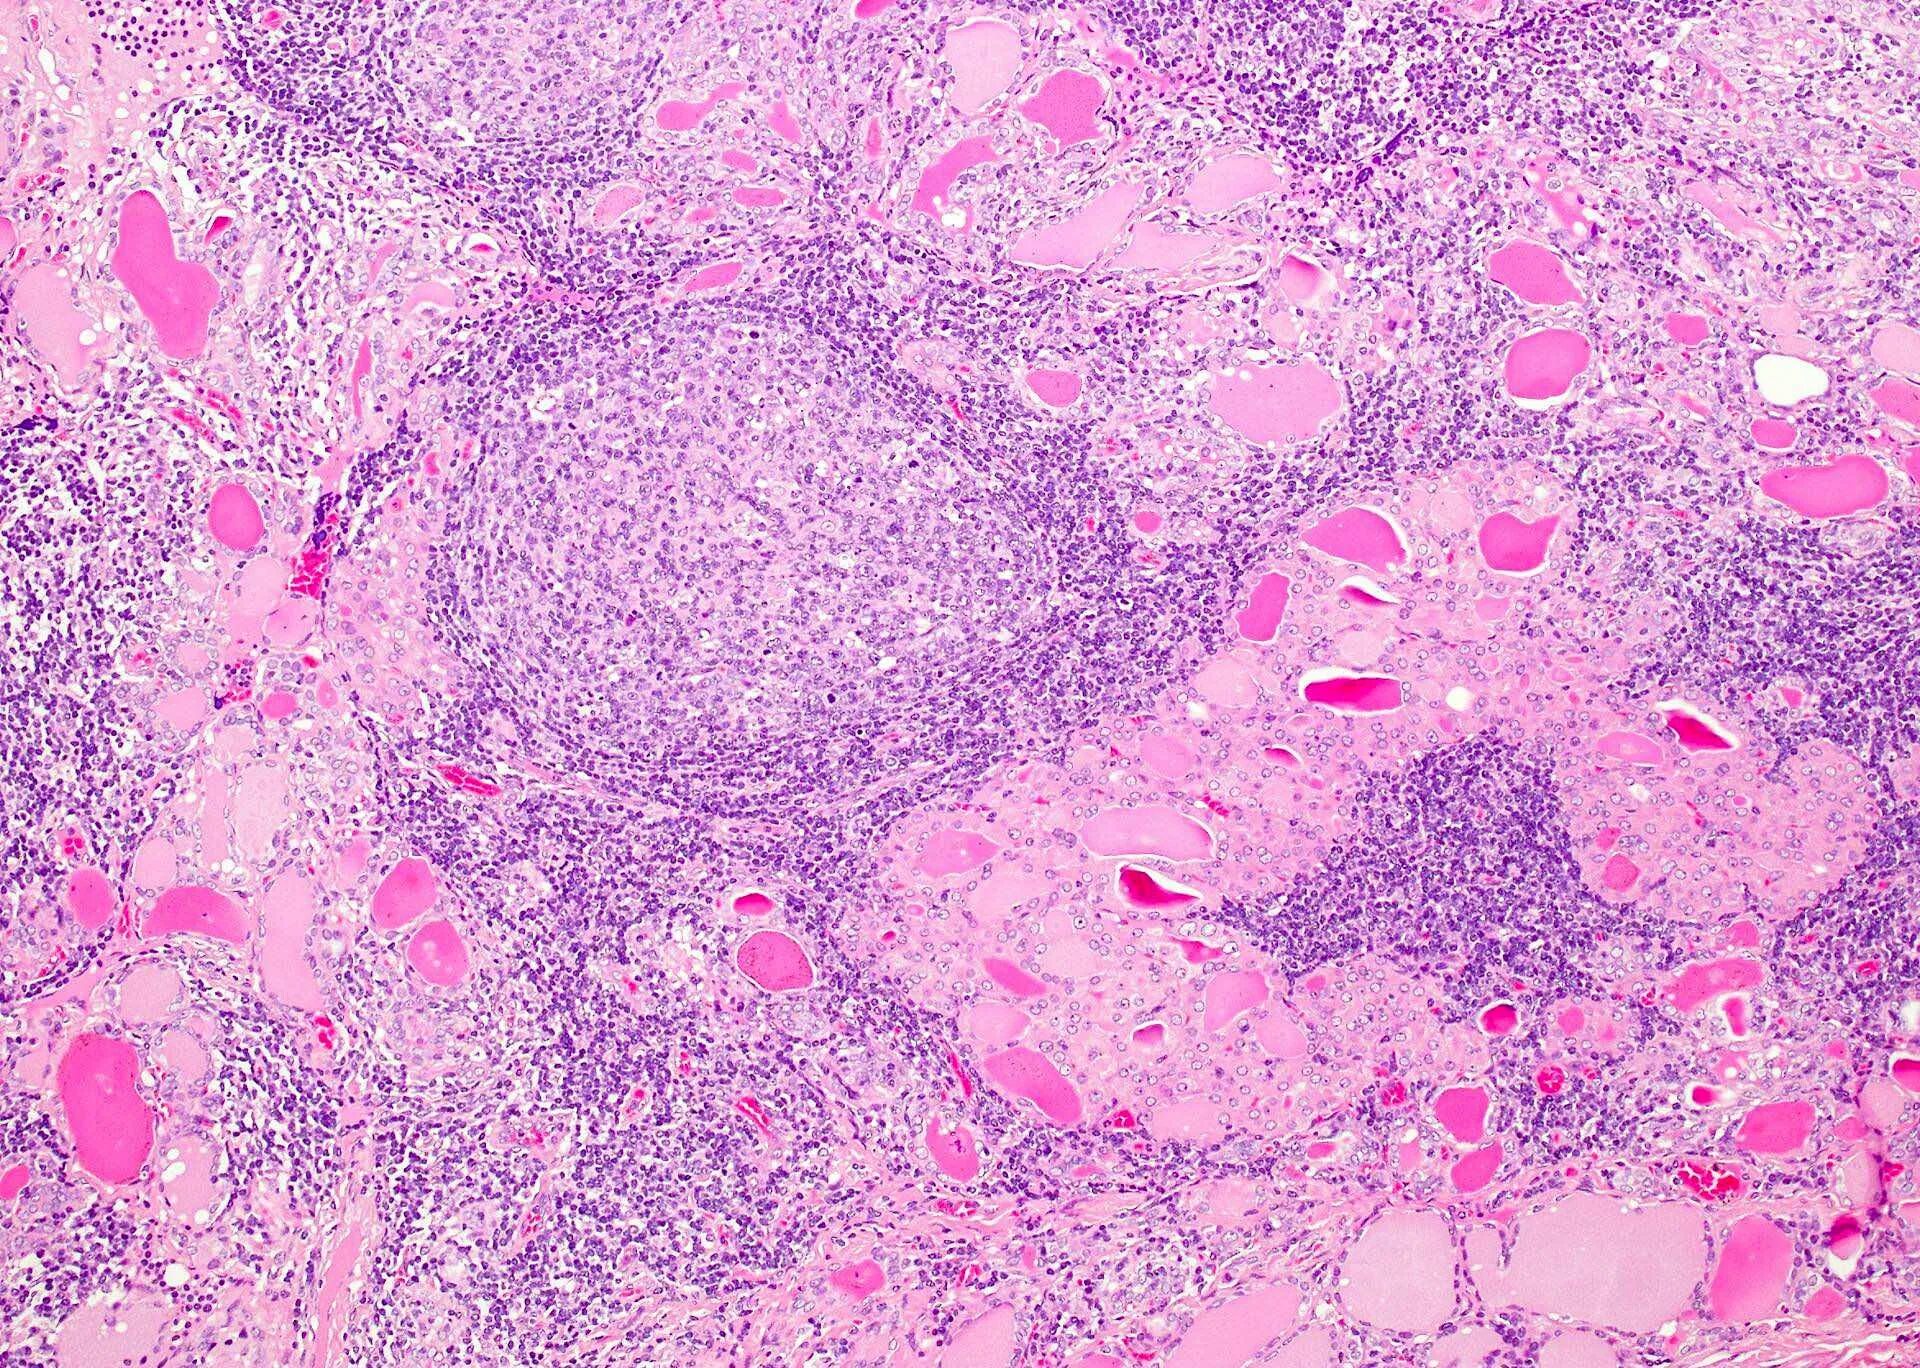

Гистология месяц